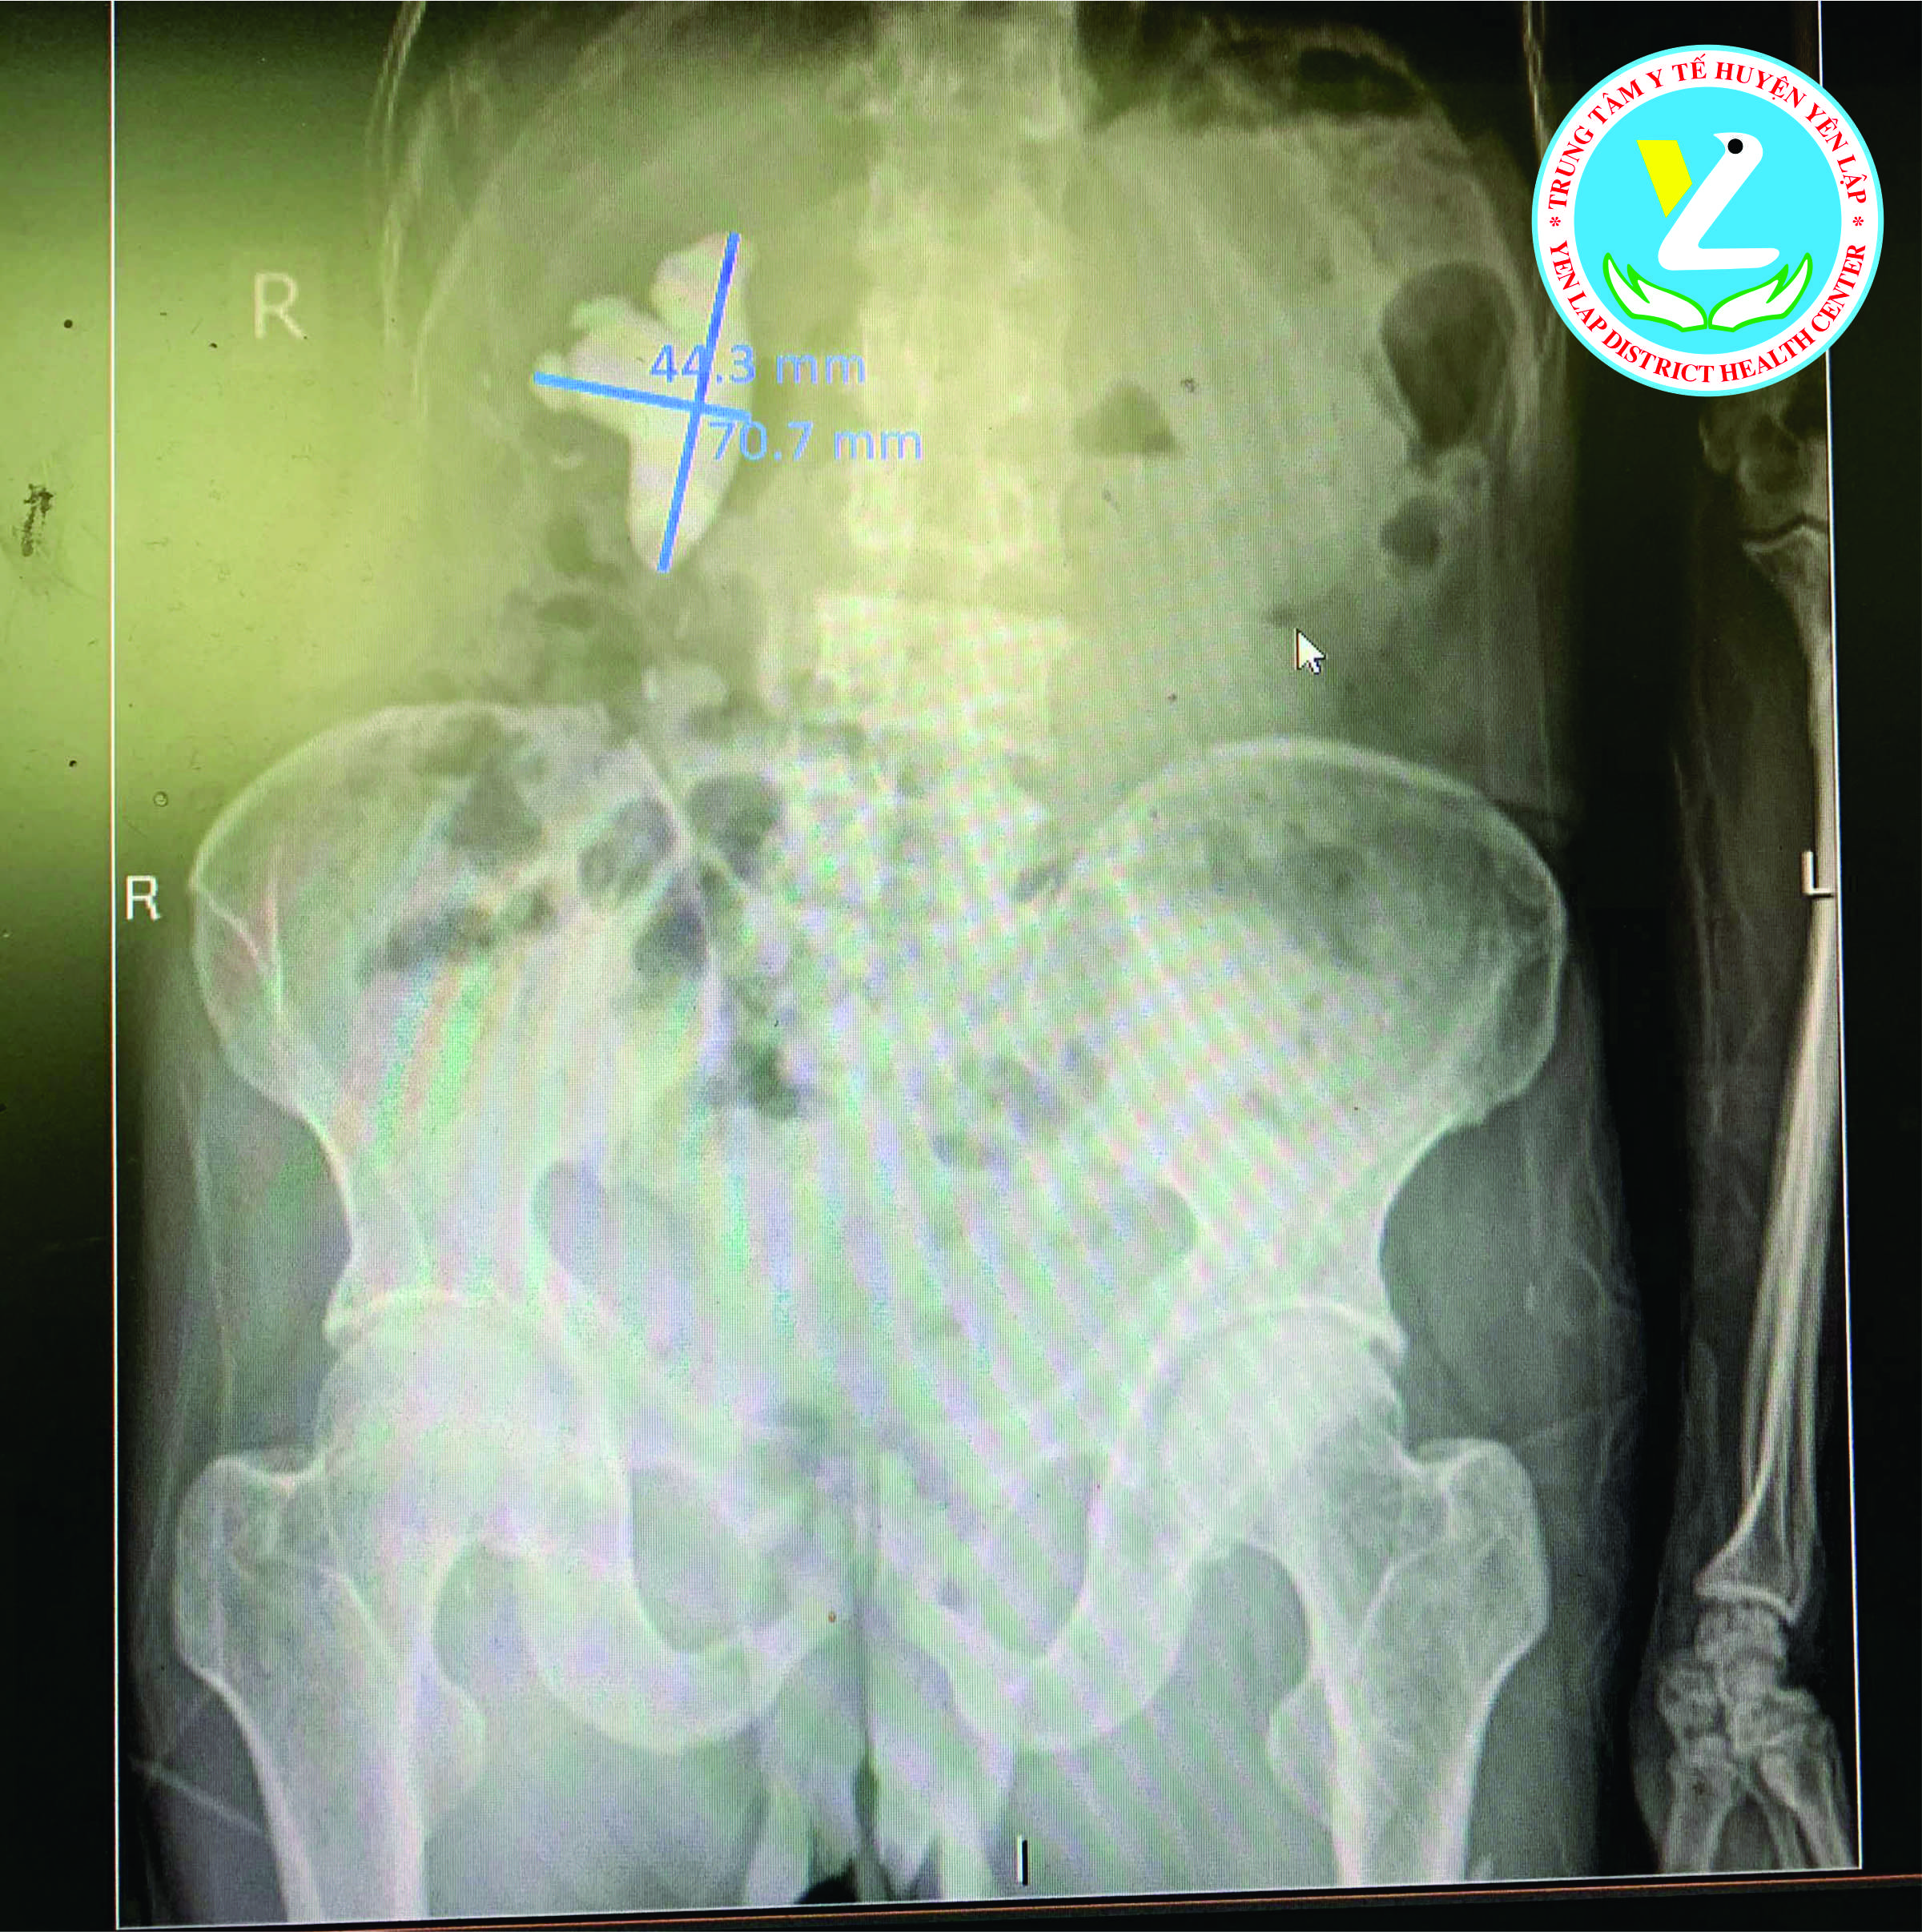

Ông Phùng Văn Minh, 66 tuổi, ở xã Thượng Long, huyện Yên Lập nhập viện với triệu chứng đau dữ dội từng cơn từ thắt lưng đến vùng hạ sườn phải. Người bệnh cho biết thường xuyên bị đau vài năm nay, nhưng chủ quan nghĩ là “đau gió” nên chỉ dùng thuốc tại nhà. Sau khi thực hiện các cận lâm sàng cần thiết, phát hiện người bệnh thận phải có sỏi kích thước rất lớn (4,43 cm x 7,07 cm).

Ngày 09/12/2020, cùng với sự hỗ trợ của chuyên gia tuyến trên, kíp phẫu thuật ngoại tiết niệu, Trung tâm Y tế huyện Yên Lập đã tiến hành phẫu thuật lấy sỏi. Sau 01 giờ đồng hồ, ca phẫu thuật đã kết thúc thành công, lấy ra viên sỏi lớn dài hơn 7cm, nặng hơn 100 gram (01 lạng)